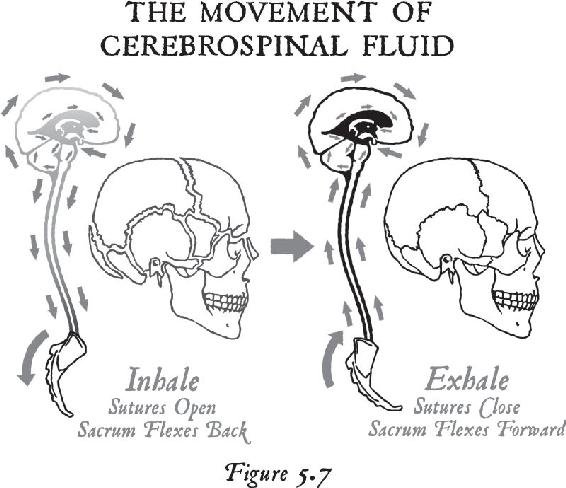

In Chapter 5, I introduce you to a breath that we use at the start of many of our meditations. This breath enables you to change your energy, run an electrical current through your body, and create a more powerful electromagnetic field around you. As I will explain, most people’s energy is stored in the body because they have conditioned their body to become the mind from years of thinking, acting, and feeling the same way. It is this process—related to living in survival mode—that causes most of the creative energy to be rooted in the body. Therefore, we must have a way to pull that energy out of the body and deliver it back to the brain, where it will be available for a higher purpose than mere survival.

I’ll give you the physiology of the breath so you can put more intention behind it when you begin to free yourself from the past. Once you start to liberate all that energy back into the brain, then you will learn how to recondition your body to a new mind. I’m going to show you how to teach your body emotionally how to live in the future-present reality instead of the past-present reality where we spend most of our time. Science tells us that the environment signals the gene. Since emotions are the chemical end products of experiences in our environment, when you embrace elevated emotions in your meditations, you will not only raise your body’s energy, but you will also start to signal new genes in new ways—ahead of the environment.

Once you are beyond your associations to this material world and you are in the unified field—chock-full of infinite possibilities—biological systems exist for taking that energy that’s beyond the vibration of matter and turning it into imagery in the brain. That’s where the pineal gland comes in, the subject of Chapter 12. Think of your pineal gland—a tiny gland perched in the central back area of your brain—as an antenna that can transduce frequencies and information and turn them into vivid imagery. When you activate your pineal gland, you are going to have a full-on sensory experience without your senses. That internal event will be more real to you in your mind while your eyes were closed than any past external experience you’ve ever had. In other words, in order to lose yourself fully in the inward experience, it has to be so real that you are there. When this happens, this little gland transmutes melatonin into some very powerful metabolites that cause you to have that type of experience. We will study the properties of this gland and then you will learn how to activate it.